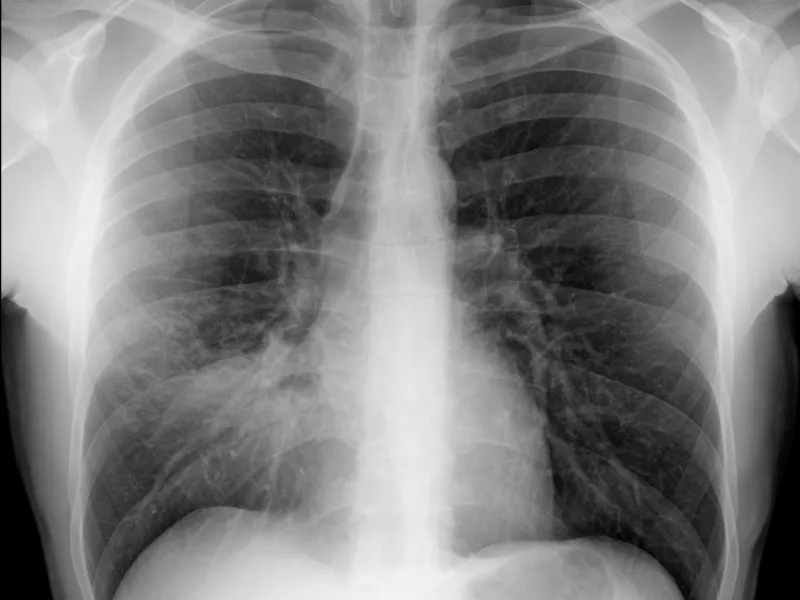

Bordes del cardiomediastino en la radiografía de tórax

Bordes del cardiomediastino en la radiografía de tórax Presentación Edad: N/A Género: Femenino Mediastino en…